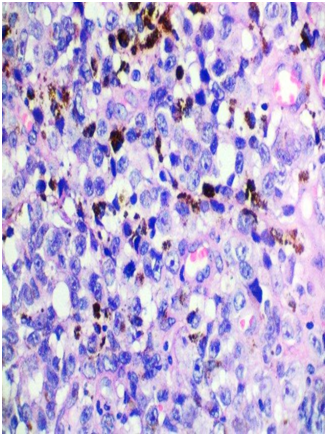

A 53-year-old female presented with one-month history of gross hematuria and increased frequency of urination. There was no past history of calculus. She did not have any medical comorbidities. She underwent hysterectomy after last childbirth at the age of 40 years. General physical examination and routine blood investigations were normal. CECT scan of whole abdomen showed 4.4x3.7x2 cm polypoid enhancing mass in urinary bladder with bladder wall thickening. Cystoscopy revealed blackish solitary papillary growth near bladder neck from 10 o’clock to 2 o’ clock position. A transurethral resection of the lesion was performed including deep muscular layers of the bladder wall. The respected specimen examination showed pigmented melanocytes infiltrating sub epithelial tissue below the transitional epithelium (Figure 1). Margins of resection were free, however, base was involved. Atypical melanocytes were seen at the margins of the tumor. Immunohistochemical study showed that tumor cells were positive for S-100 (Figure 2) and HMB-45 (Figure 3). They were negative for cytokeratin and SMA. Dermatologic, ophthalmologic, otorhinolaryngologic and proctologic evaluations were negative. Upper gastrointestinal endoscopy and colonoscopy were negative. Abdomen, chest and brain CT scans were negative. Bone scan was negative. These findings were consistent with primary malignant melanoma of urinary bladder. After thorough review of published scientific literature, we suggested radical cystectomy as the therapeutic option. The patient declined any further treatment so was given only symptomatic & supportive treatment. Nine months later, she presented with hematuria and back pain. PET-CT showed increased uptake in lumbosacral vertebrae and liver, suggestive of metastases. She was advised palliative radiotherapy to the painful bone metastases and continued to receive palliative care. She succumbed to complications caused by widespread metastases fourteen months after the diagnosis.

Figure 1 Hematoxylin and eosin, x45X; malignant melanocytes with melanin pigment.

Regarding histological diagnosis, the microscopic examination of malignant melanoma reveals spindle or epitheloid cells. Epitheloid cells have marked pleomorphism, abundant cytoplasm, and prominent eosinophilic nucleoli. Cytoplasmic melanin pigment can be seen. Often atypical melanocytes are seen.